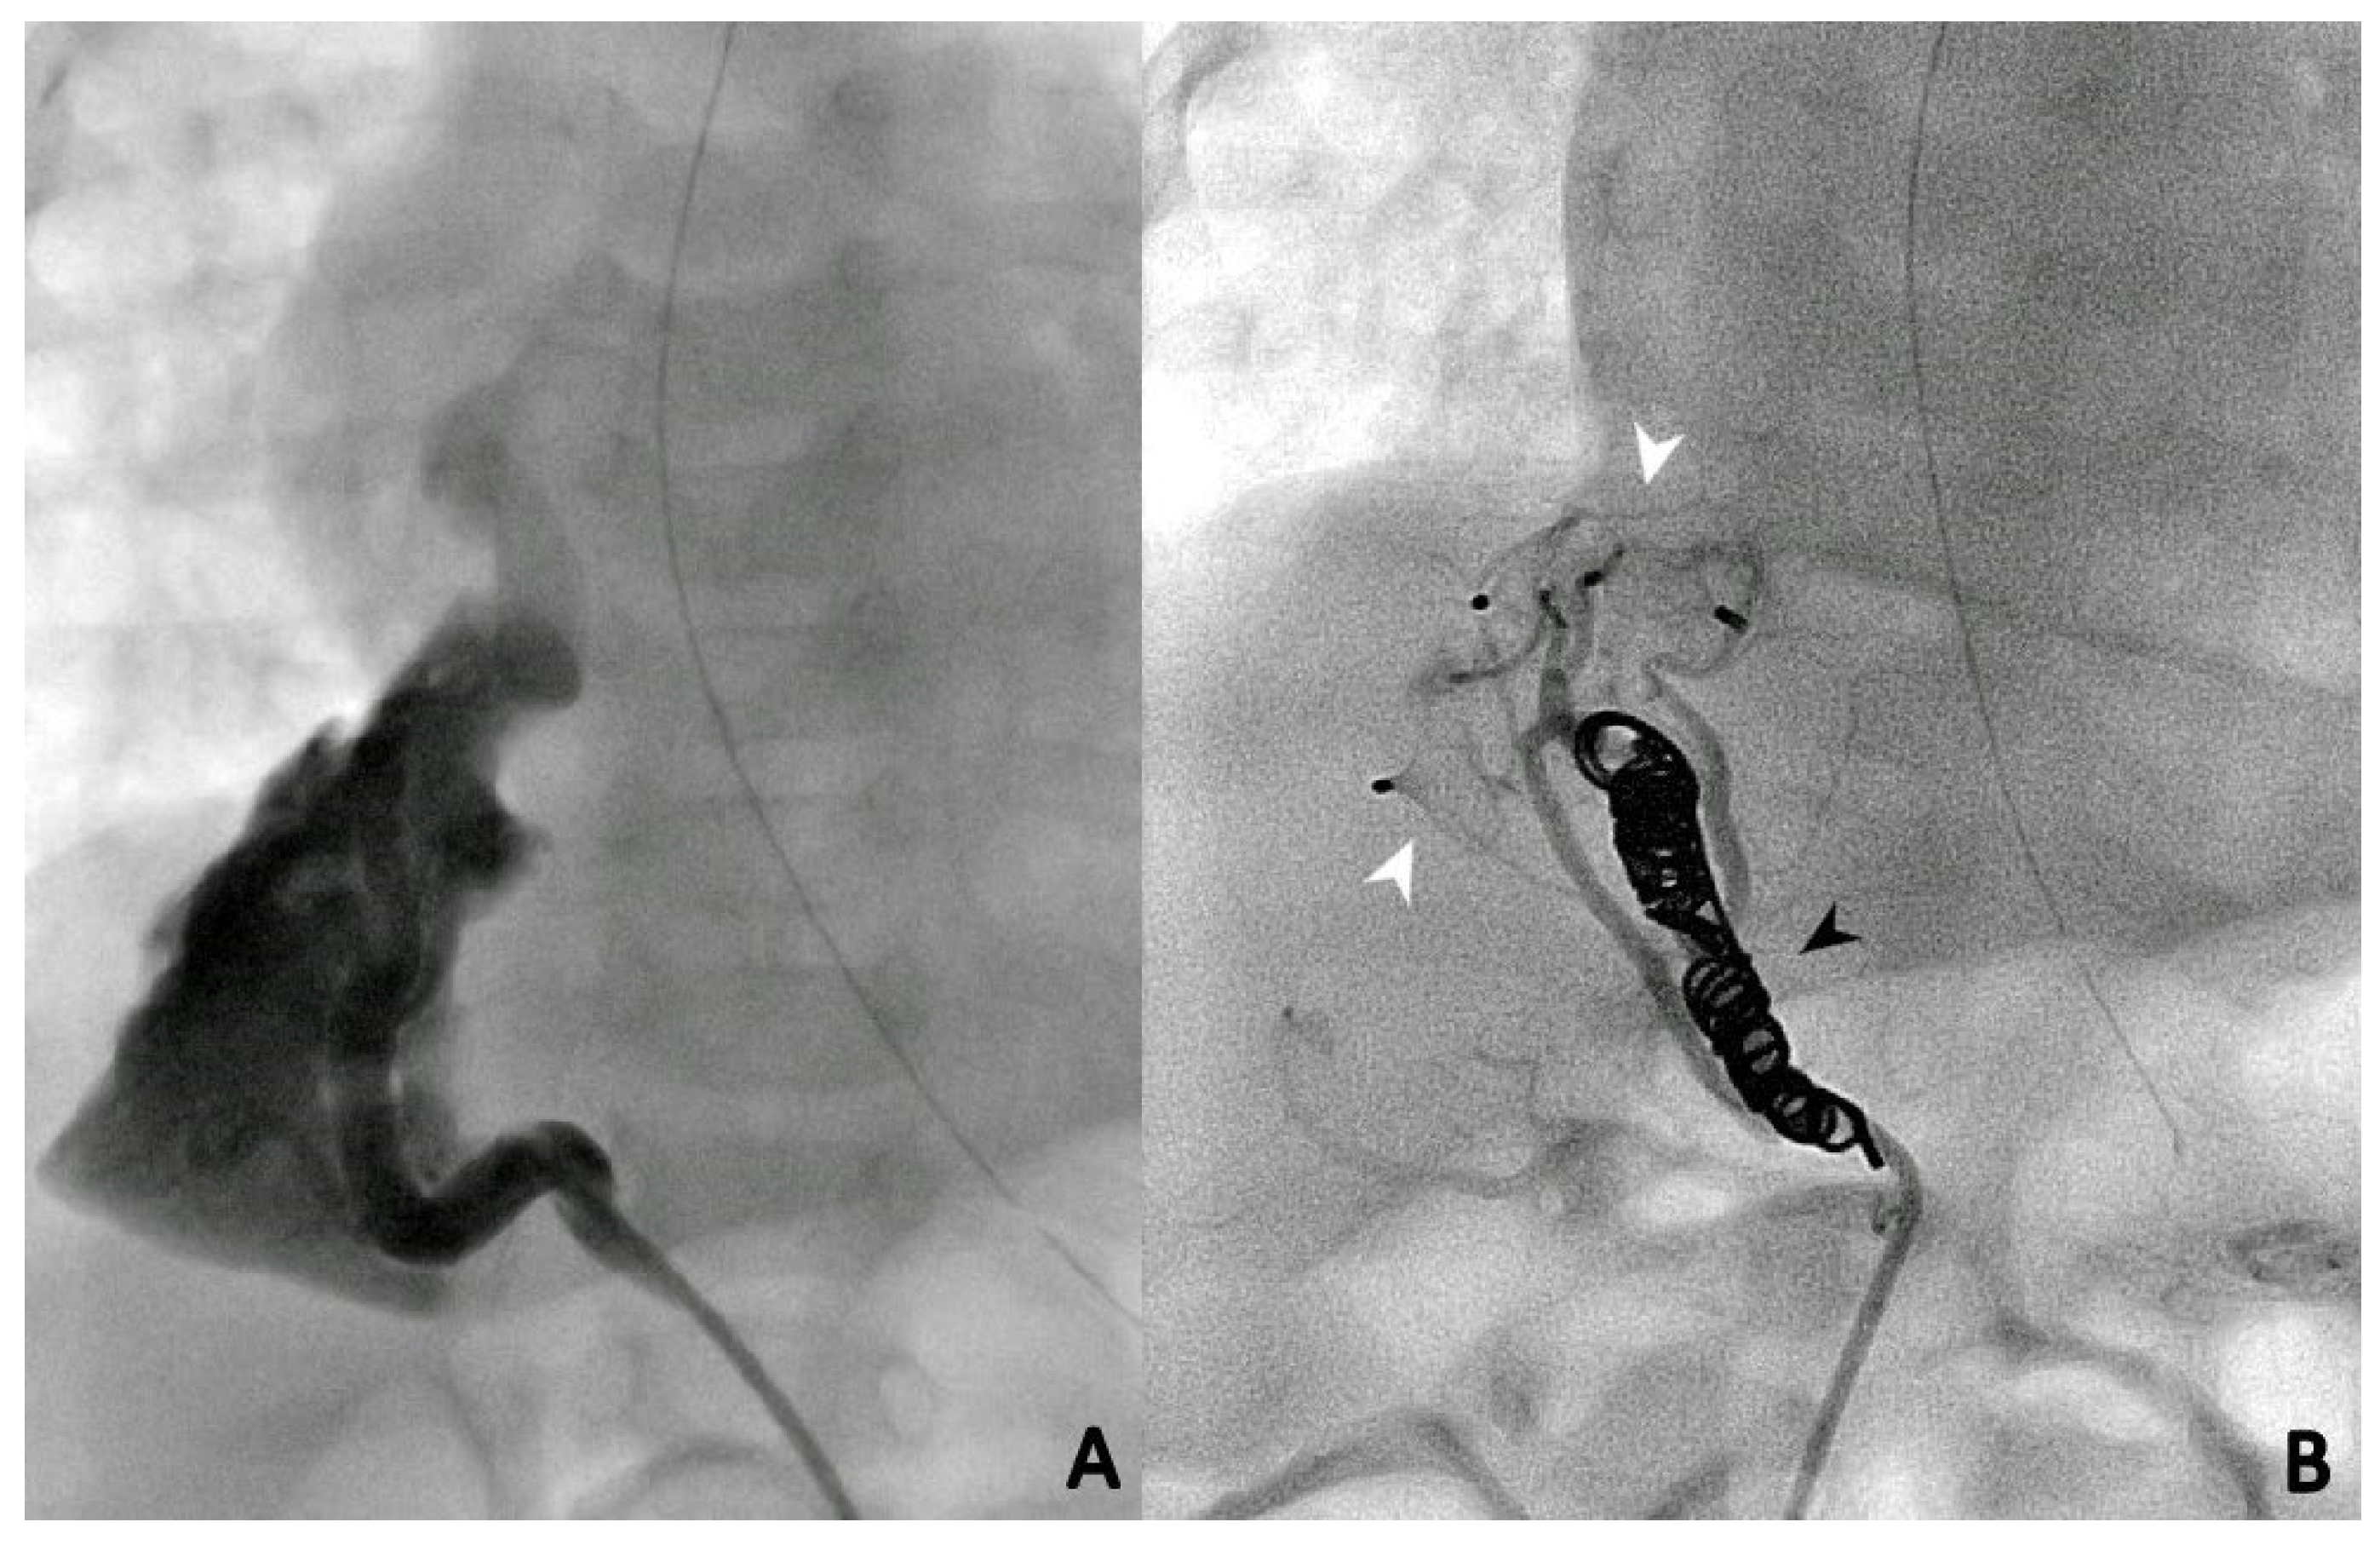

3.3. Endovascular Embolization

During the first procedure, 47/71 (66.2%) patients underwent endovascular embolization of the PS feeding vessel (Figure 1, Figure 2 and Figure 3). The type and number of occluder vascular devices are detailed in Table 3. In 14/47 (36.2%) patients, occlusion was achieved with a combination of vascular plugs and micro coils (Figure 1, Figure 2 and Figure 3). Reasons for non-embolization or delayed embolization are also described in Table 3. In 21 cases, the feeding vessels were too small or without hemodynamic significance. The feeding vessels were too large for endovascular treatment (no suitable device available on the market at the time of catheterization) in two patients (Figure 4), and one patient was hemodynamically unstable, leading to abortion of the embolization procedure. One coil migrated and was recaptured by snare. One patient experienced transient atrioventricular block during right heart catheterization. Procedure time and radiation exposure are detailed in Table 3. The median hospital stay was 3 days (IQR, 2–8).

Microcoils (Figure 1), vascular plugs (Figure 2), and a combination of both (Figure 3) were our devices of choice to embolize the PS-feeding arteries. Polyvinyl alcohol (PVA) particles, gelatin sponge, alcohol, glue (n-butylcyanacrylate), and various combinations of embolic materials have also been reported [12,16,17,25,27]. However, the high-flow nature of such anomalies and their drainage into pulmonary veins in many patients require embolic products with a low likelihood of distal embolization or migration. Microcoils are currently the most used embolic agents for vessel anomalies in many institutions. However, super-selective endovascular occlusions using microcoils can sometimes be challenging due to anatomic considerations. In high-flow arterial vessels such as PSs, numerous coils can be required for complete occlusion. On the other hand, new-generation low-profile microvascular plugs allow us to treat these vessels using microcatheters with diameters of 6–7 mm [27]. Using these devices, we were able to track smoothly through tortuous vessels and keep arterial access at a maximum of 5 Fr. A combination of microvascular plugs and microcoils has been also effective in larger feeding vessels, where we packed the vascular plugs with long microcoils if persistent flow was demonstrated by control angiographies.

Figure 1. Selective angiographies before (A) and after (B) closure of the PS feeding vessel using multiple Concerto microcoils (Medtronic, Minneapolis, MN, USA) of various sizes.